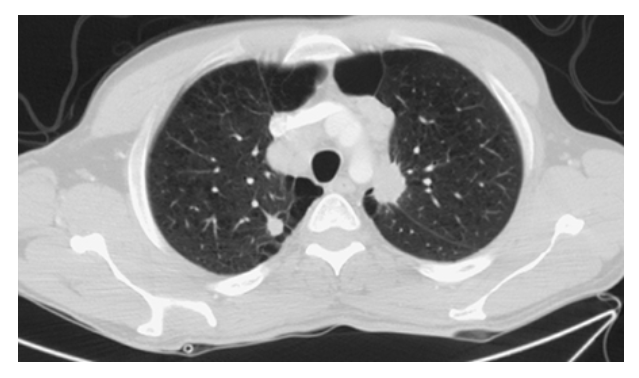

Bronchogenic Carcinoma. CT of the chest with lung windows shows bilateral round pulmonary nodules with irregular speculated margins.